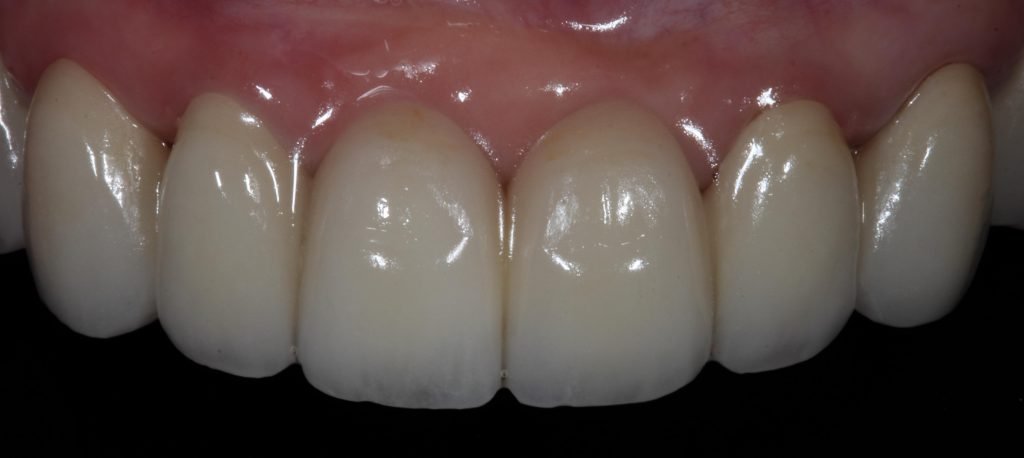

Punto Bajío Casos Clínicos Prótesis Fija sobre Implante unitario Inicio Provisional Final Prótesis Parcial Fija sobre 2 Implantes 2 Implantes Final Prótesis Bucal Removible Inicial Inicial Superior Inicial Inferior Rayos X Inicial Rayos X Inicial Frontal Final Final Superior Final Inferior Prótesis Parcial Fija/ Coronas de Circonio Sonrisa Inicial Foto Inicial Foto Inicial Inferior Foto Final Inferior Foto Final Sonrisa Final Prótesis Total Protesis Inmediatas 1 Protesis Inmediatas 2 Prótesis Removible/ Coronas Metal-Ceramica Carillas Incrustaciones Endodoncia